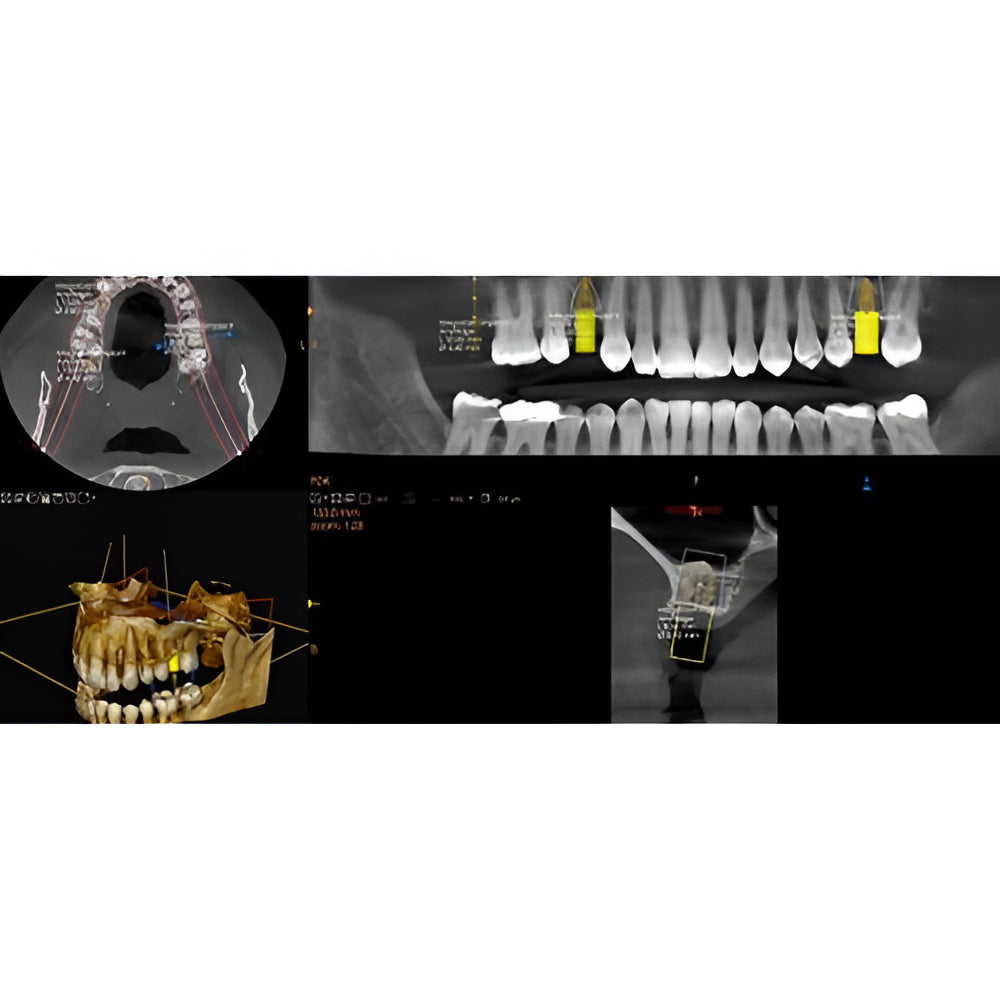

Enter a world of crystal-clear 3D images with the CS 8200 3D Access-a CBCT system that’s state-of-the-art, but intuitive and easy to use, taking your dental practice to the next level. Enjoy CBCT imaging that’s easier than you think and built on an open platform so that you can activate your future practice here and now.

- Field Of View: 4x4, 5x5, 8x5, 8x9, 12x5, 12x10

- Versatile 4-in-1 solution ideal to expand treatment options

- Easy to use with a modern, user-friendly interface

- Built on an open platform for a seamless workflow